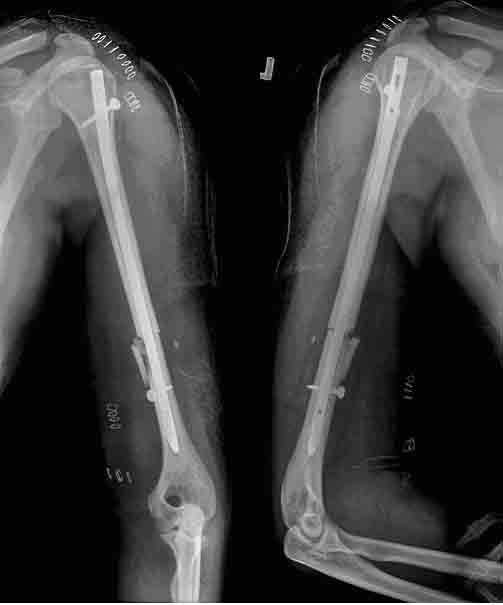

(Figure-1)

Union: Twenty eight of the 37 fractures united within four

end of 6 months (Figures 1-3).

(Figure-2)

bone grafting. The second

nonunion was an open type 2, AO type A3 fracture and he had come

back with a broken nail at the level of the fracture at 6

months. The third nonunion was an open type 3B, AO type B3

fracture. These two patients underwent nail removal, plating &

bone grafting and they were rated as poor outcome because of the

failure of the nail to achieve union.

(Figure-3)